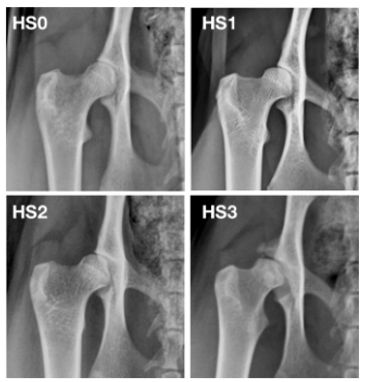

The evaluation grades on the scale used are the same ones as for hip radiographing dogs, but due to the fact that the anatomical picture is different for cats the usual "Norberg’s angle" is not used. This means that we do not use the ABCD evaluation scale. Instead, we use "normal", "1", "2" and "3" where each hip will be scored separately:

Where hip scores are borderline, these cats are always graded at the lower score: i.e. scores were conservative in these cases.